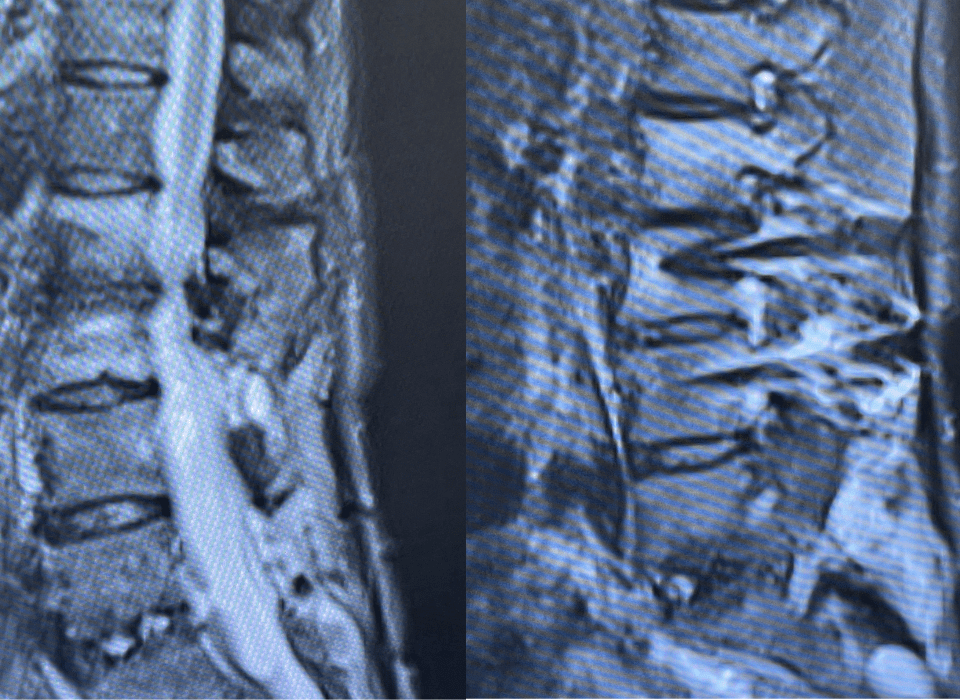

A 55-year-old woman presented with acute onset of severe headache, and possible witnessed seizure. Imaging confirmed intraventricular hemorrhage primarily focused within the fourth ventricle with diffuse […]